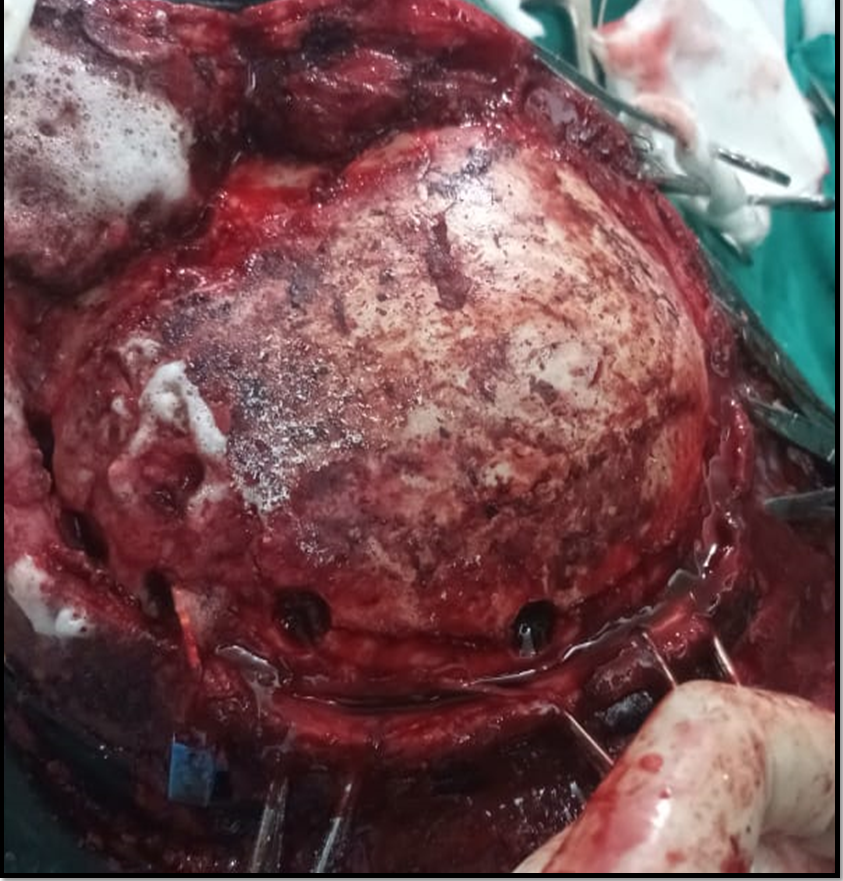

As per our protocol ICP surge greater than 25mmHg, resistant to conservative therapy, decompressive craniotomy was planned.

Upon lifting the bone flap there is a minimal drop in both values but still in high range.

As durotomy is done, both ICP and ICP A again plummet to the normal values, also evidenced by the graph.